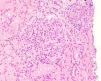

Once proteinuria was confirmed, a renal biopsy was performed that showed glomerular hypertrophy without sclerosis, enlargement of the glomerular capillaries and the presence of sickle cells within the capillaries (Fig. 1). The tubules have cells with haemosiderin by Perls staining and occasional areas of atrophy associated with fibrosis seen with trichrome staining (Fig. 2A and B). Interstitial vessels do not reveal abnormalities and direct immunofluorescence shows absence of deposits.

In addition to the more frequent form of glomerulopathy (FSG), it may be manifested as membranoproliferative glomerulonephritis, thrombotic microangiopathy and sickle cell-specific glomerulopathy.2,8 Biopsy is rarely used to establish the diagnosis; in early sickle cell nephropathy, glomerular hypertrophy is observed and is part of sickle cell disease description in 1960; the most frequent location of glomerular hypertrophy is at the juxtaglomerular level, in addition there is tubular hemosiderin deposits that play a relevant role in the progression of the nephropathy. Other microscopy findings include red blood cell sickling in vasa recta, capillary congestion, mesangial expansion and endothelial lesion expressed as expansion of the lamina rara interna. Renal biopsy is necessary in cases of significant proteinuria (>1g/day) or rapid deterioration of renal function that suggests glomerulonephritis.